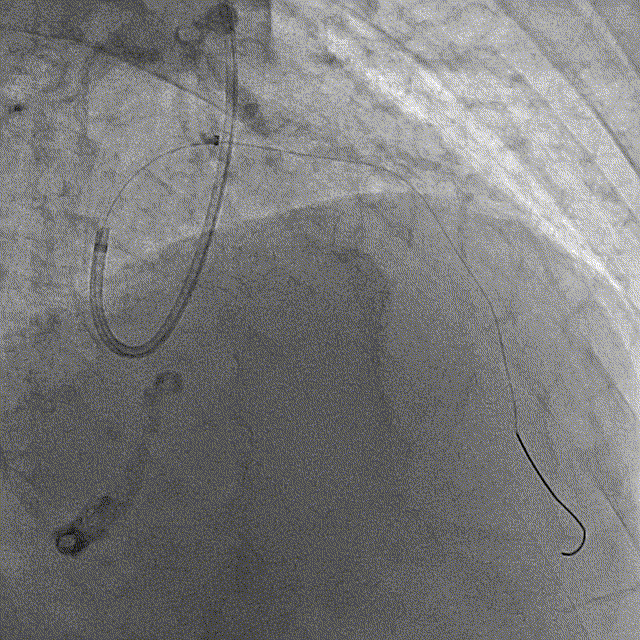

冠脉造影结果:LM外膜钙化,内膜不光滑,中段狭窄90%,TIMI3级。LCX外膜钙化,内膜不光滑,TIMI3级。RCA外膜钙化,内膜不光滑,近段狭窄80%,中段狭窄90%,可见破损斑块,TIMI3级。

冠脉内介入治疗